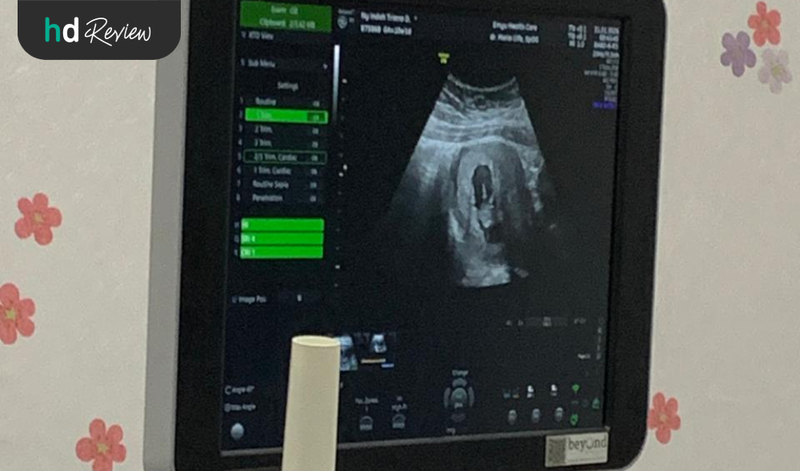

USG adalah pemeriksaan kehamilan yang dilakukan untuk memantau kesehatan janin dalam kandungan. Momen ini bisa menimbulkan ketegangan, rasa penasaran, sekaligus semangat para calon ibu saat melihat si Kecil. Jika ini pengalaman USG kehamilan kamu untuk yang pertama kalinya, review USG 4D di Emyu Healthcare dari Indah ini bisa memberikan gambarannya.

Sebagai calon ibu, Indah sempat merasa deg-degan sebelum menjalani USG perdananya. Proses USG 4D menunjukkan ukuran dan berat janin dalam kandungan. Menurutnya, pemeriksaan kesehatan ini dilakukan dalam waktu yang tidak lama--kurang lebih hanya 10-15 menit.

Hasil USG 4D menunjukkan bahwa janinnya dalam kondisi sehat. Pelayanan tim dokter juga baik dan detail, membuat pengalaman USG kehamilan ini memuaskan.

Gerakan, bentuk wajah, dan anggota tubuh janin terpampang dengan jelas dan real-time. Orang tua mana yang gak excited lihat bayinya bergerak, tersenyum, membelakangi, bahkan cegukan dari layar monitor. Pengalaman ini bisa kamu rasakan dengan memilih USG 4D.

Pemeriksaan USG itu pakai sebuah alat transduser yang mengeluarkan gelombang suara berfrekuensi tinggi. Berkat gelombang suara inilah, kita bisa melihat gambaran dalam tubuh, seperti organ atau jaringan lunak pada ibu hamil dan janin.

Sebelum pakai alatnya, biasanya perawat atau dokter akan mengoleskan semacam gel dingin ke permukaan perut. Gel ini tugasnya sebagai penghantar gelombang suara dari transduser supaya bisa memperlihatkan gambar dengan lebih jelas.

Setelahnya, alat transduser akan ditaruh di perut dan diarahkan ke segala sisi yang ingin dilihat bagian dalamnya. Tangan kanan 'menyapu' area, tangan kiri dokter fokus ke kursor dan tombol di mesin USG-nya.

Di sini dokter bisa dapatin gambaran banyak hal pada janin, mulai dari ukuran sampai berat badan. Prosesnya juga terbilang cepat, kurang lebih hanya 10-15 menit. Intinya sih, sampai semua informasi bisa didapatkan dengan optimal dan jelas.